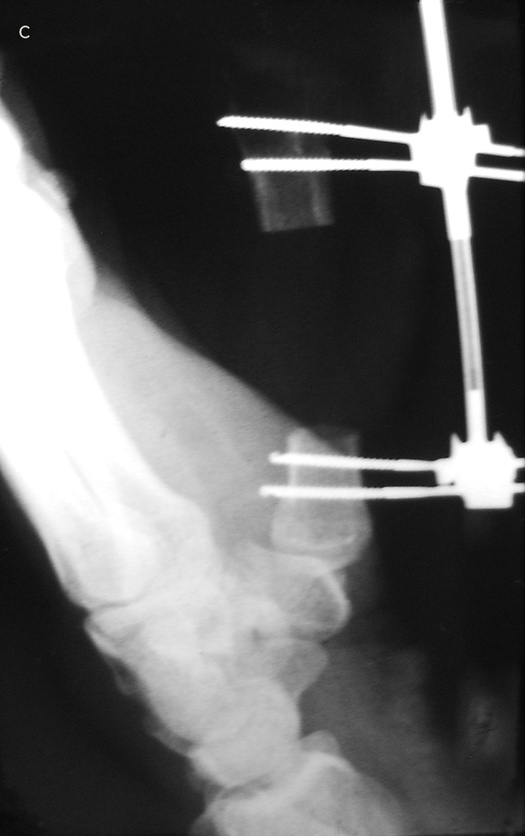

Если восстановить или приживить эту важнейшую часть кисти невозможно, ее реконструируют. Существует три основные методики, которые я условно называю «упросить», «одолжить» и «украсть». В первом случае хирург и пациент как бы упрашивают обрубок большого пальца вырасти в длину. С обоих концов оставшейся кости хирург вставляет поперечные стальные шпильки, прикрепляет эти шпильки к стальной раме и разрезает кость между ними.

Пациент каждый час поворачивает небольшую ручку этого приспособления, напоминающего аппарат Илизарова, и по чуть-чуть увеличивает промежуток между фрагментами кости. Процедура длится от шести до восьми недель. Кость и окружающие ее мышцы, сухожилия, нервы и кожа едва ли понимают, что их растягивают: для них это просто какой-то очень быстрый рост, и им надо успеть.

Когда большой палец вновь обретает рабочую длину, хирург заполняет промежуток костным трансплантатом. Преимущество такого способа удлинения в том, что не приходится ничего «одалживать» или «красть». Однако не все так радужно: ноготь и отсутствующие суставы большого пальца уже не вернуть.